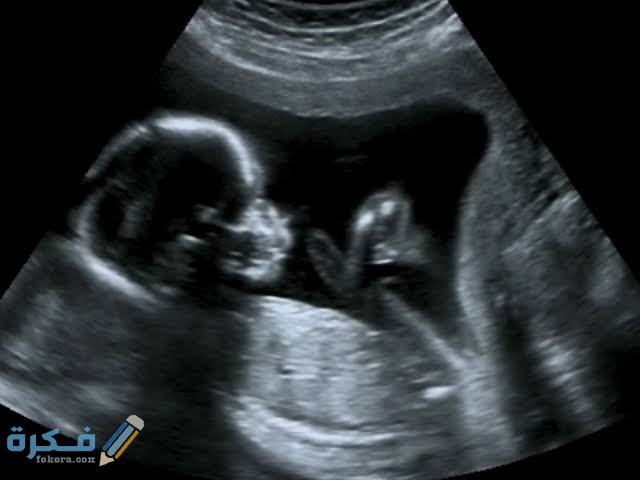

السونار في الشهر الرابع

السونار هو عبارة عن موجات فوق صوتية يتم من خلالها تصوير رحم الام وهو له أهمية كبيرة في عملية الحمل وتكمن أهمية السونار في النقاط الآتية :

كم نسبة صحة السونار في الشهر الرابع

- بحسب أراء العلماء والأطباء حول العالم ان السونار هو من أفضل الوسائل لتحديد نوع الجنين وليس هذا فقط بل انه الوسيلة الأمنة والفعالة التي من خلالها يمكن للطبيب أن يرى الأعضاء التناسلية للطفل ويحدد نوعه.

- فيعمل السونار بالموجات فوق الصوتية التي تمنح الطبيب صورة واضحة لكل أعضاء الجسم ومع نهاية الشهر الرابع تكون الأعضاء قد اكتملت ويمكن تحديد نوع الجنين.

شكل الجنين الأنثى السونار في الشهر الرابع

إن تحديد الجنين الانثى يكون أصعب من الجنين الذكر وحتى يمكن تحديد شكل الجنين الأنثى فستلاحظ وجود ثلاث خطوط و هذه الخطوط تمثل شفرات البظر.

شكل الجنين الذكر السونار في الشهر الرابع

تحديد الجنين الذكر أسهَلْ كثيرا من البنات، حيث أن تحديد شكل الجنين الذكر يكون ذلك من خلال رؤية العضو التناسلي للذكر والذي يمكن تحديده ورؤيته بسهولة.